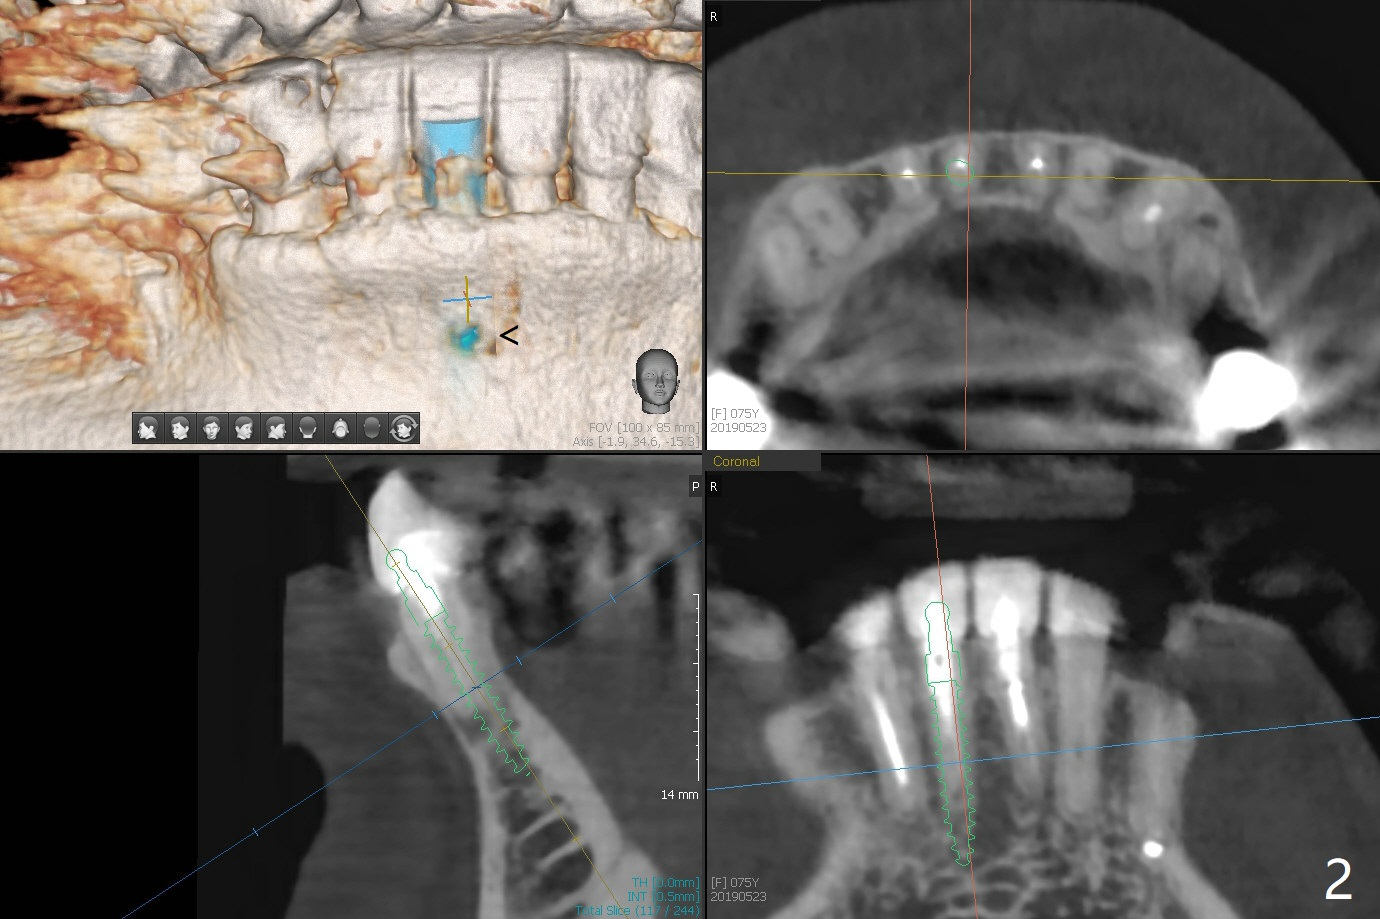

2.5x14(2) mm Implant

A 75-year-old woman with history of full mouth reconstruction requests implant for the tooth #25 with horizontal fracture with PARL (Fig.1-3).